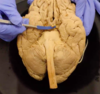

What is being pointed to?

Corpus callosum